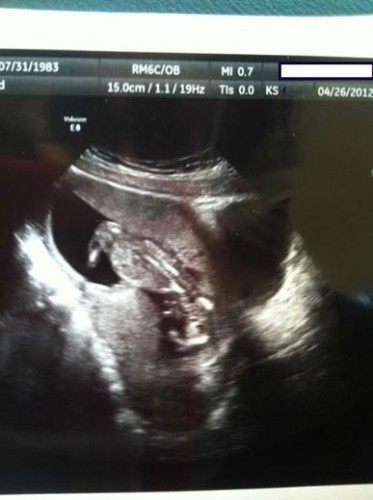

Şimdi de ultrasonda bebek yerine bir ördek gördüğünüzü düşünün. Merak etmeyin, aslında sadece “pareidolia” sendromunu yaşıyorsunuz.

İşte bebek ultrasonlarında çekilen ve bazı anne babalara mini kalp krizi geçirten bebek fotoğrafları!